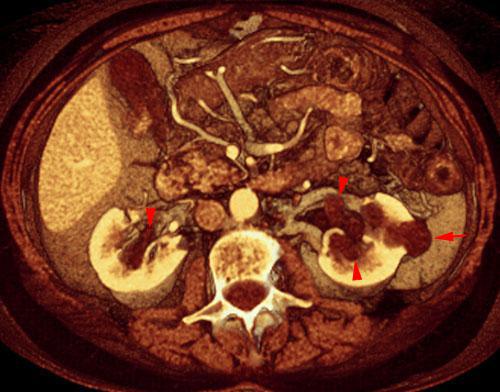

Quistes renales pielosinusales

VR seccional. Visión axial caudal. En ambos senos renales se visualizan quistes pielosinusales (puntas de flecha) que no deben ser confundidos con dilataciones pielocaliciales. Existe asociado un pequeño quiste cortical izquierdo (flecha)